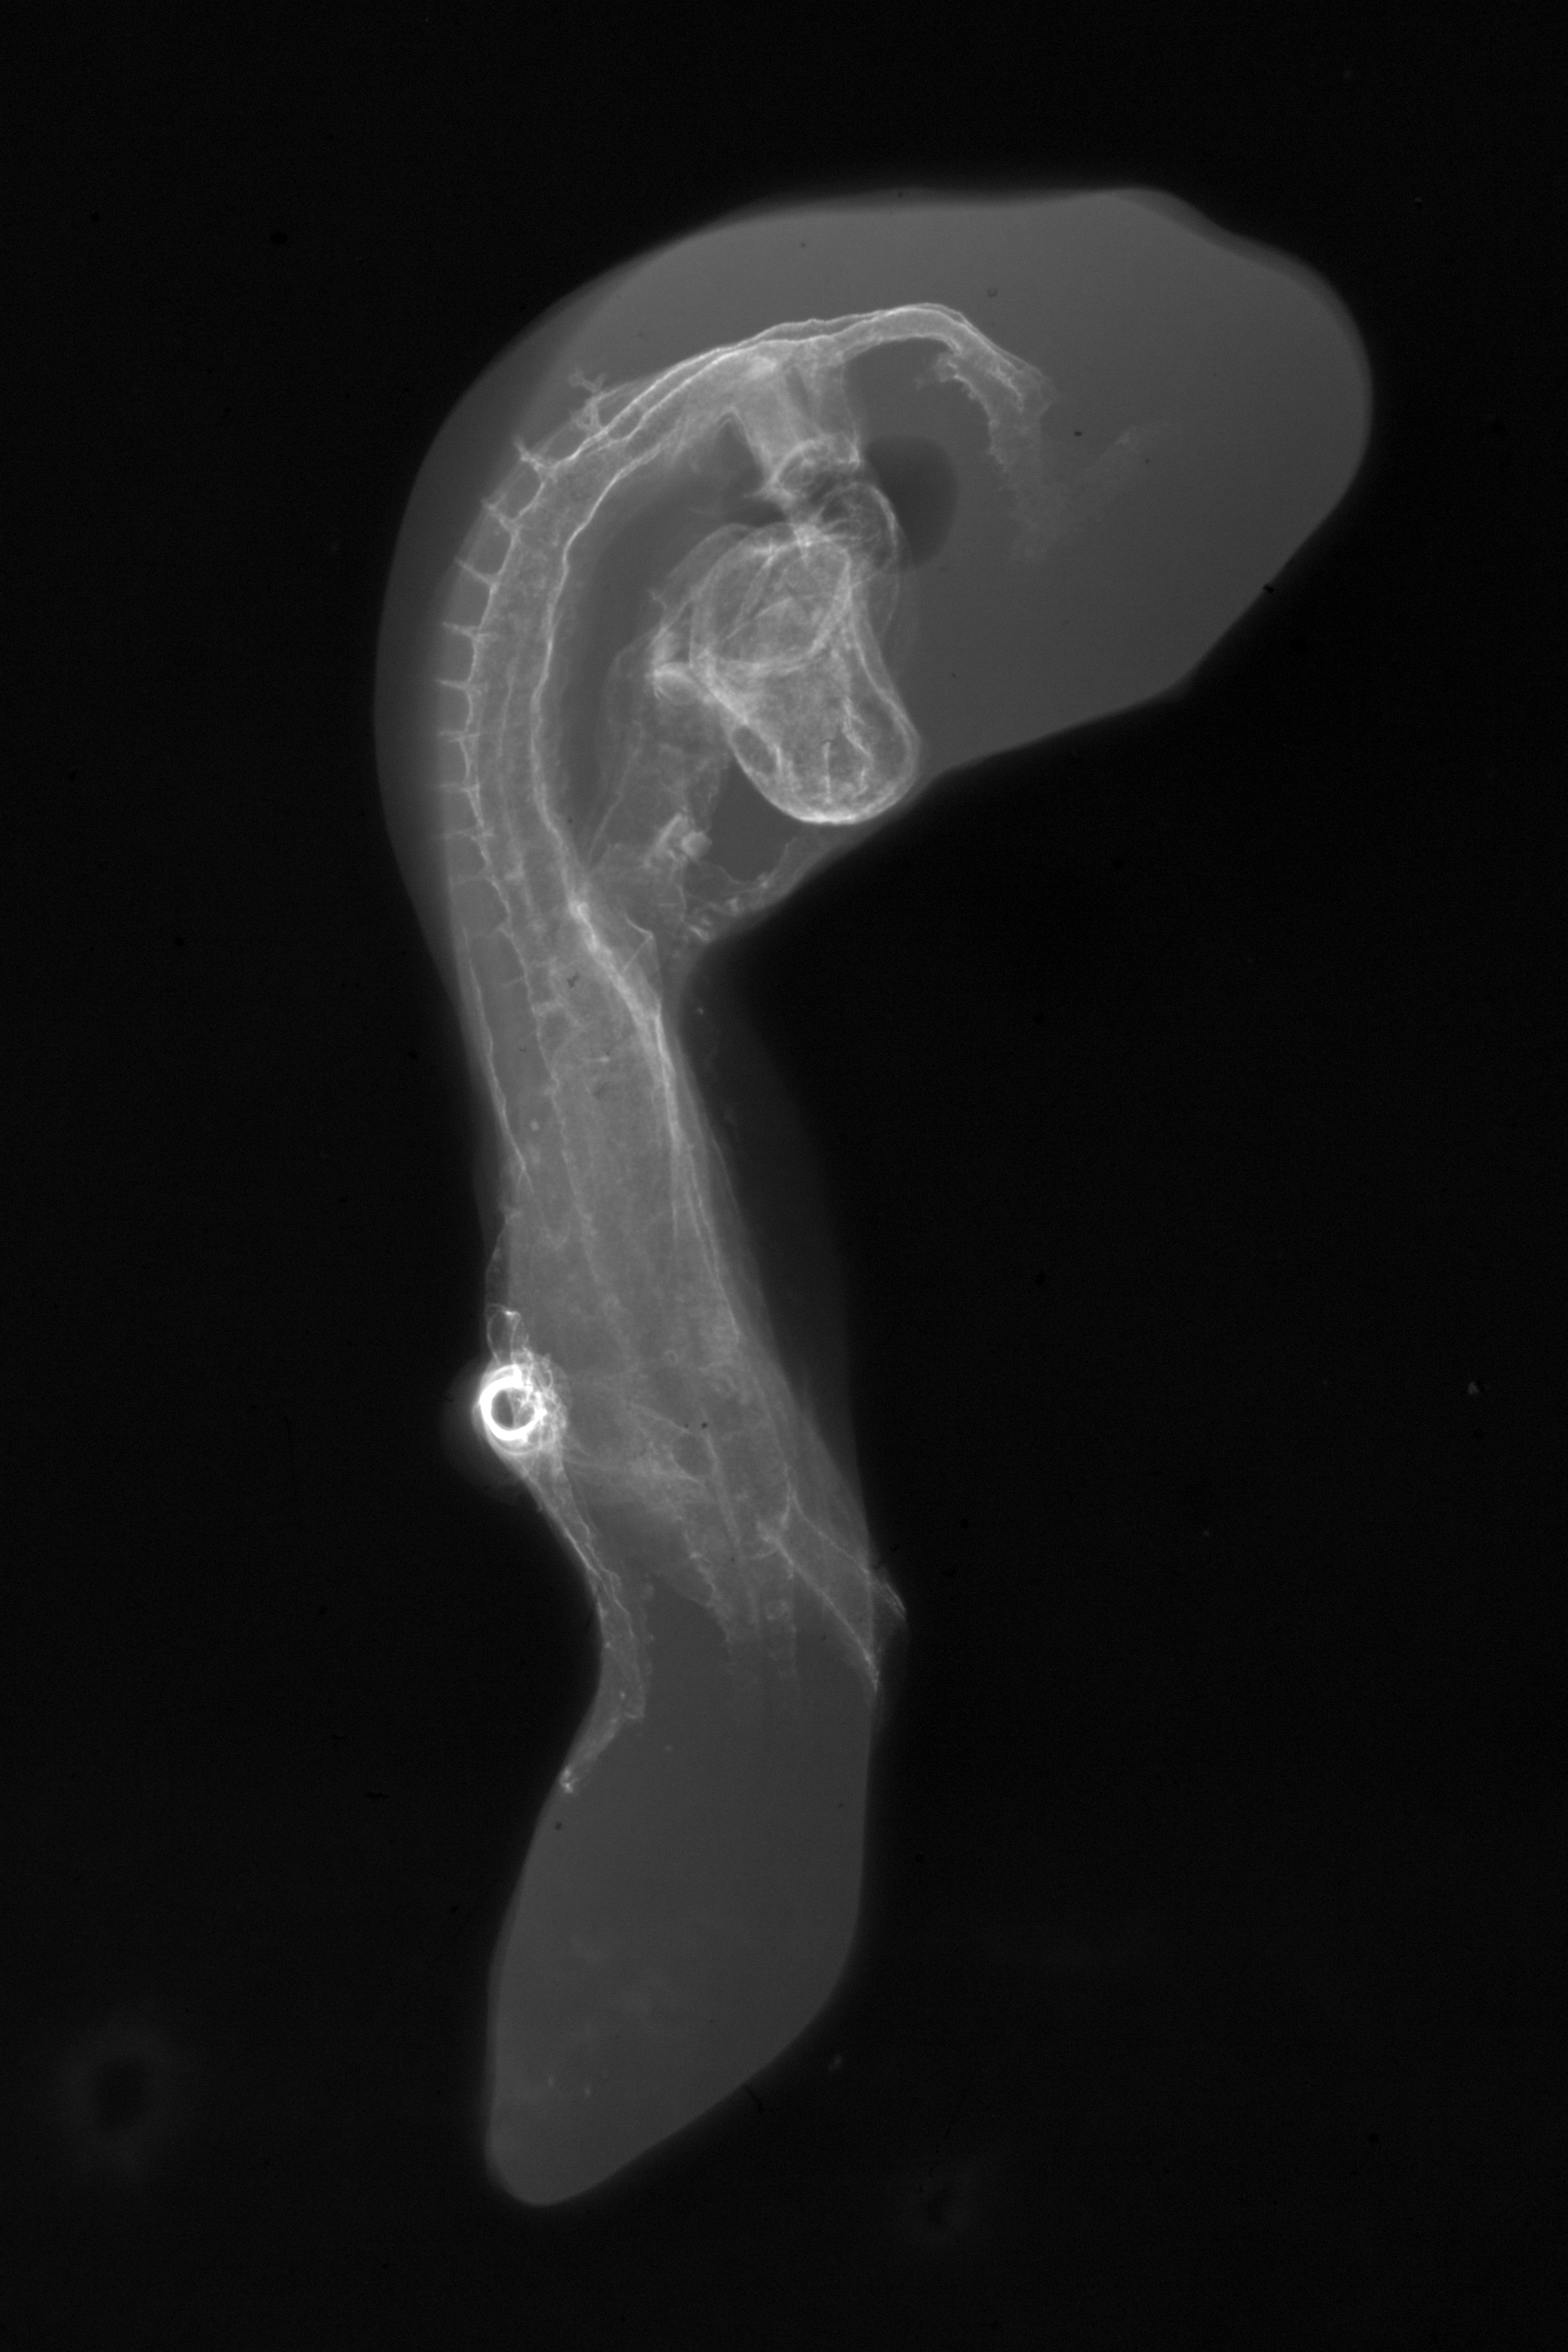

Chick Embryo Microangiography

Hamburger-Hamilton (HH) Stage 16 (approx. 2.1 - 2.5 days)

Stereo X-Ray Micrographs